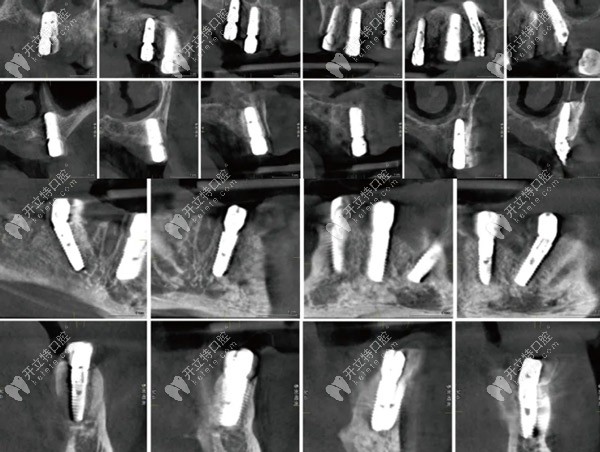

術(shù)后即刻CBCT種植體冠狀、矢狀面影像

術(shù)后即刻CBCT種植體冠狀、矢狀面影像▲

下頜導板固定后先鋒鉆備洞,骨修整于35,32,42,45位點植入Osstem Ts植體4.5-13mm(2顆)、4.0-11.5mm(2顆)所有的植體初期穩(wěn)定性均達到35Ncm以上。安裝復合基臺(30Ncm)及保護帽縫合。